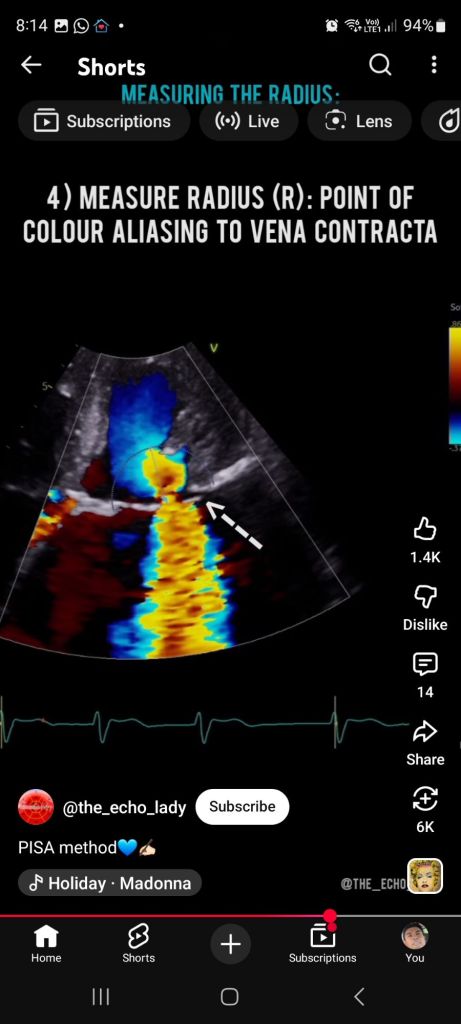

Flow accelerates toward the hole

It forms concentric hemispheric shells of equal velocity

These shells are what we call PISA.

On color Doppler:

Flow suddenly changes color (e.g. red → blue)

That sharp boundary = aliasing velocity line